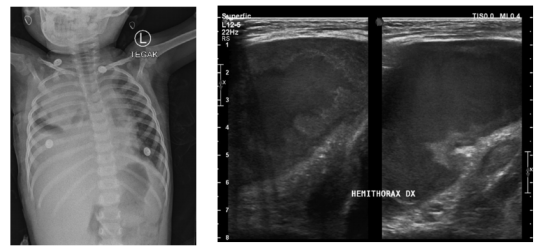

胸片检查发现大量右侧胸腔积液,可能伴有右肺不张和左肺浸润(图1)。此外,患者接受了胸部超声检查,结果显示复杂的右侧胸腔积液伴胸膜增厚,怀疑局限性胸腔积液伴右肺内侧实变(图2)。

图1. 住院第1天的胸片显示右半胸均匀混浊,左肺中上区浸润

图2. 住院第1天的超声检查显示胸腔积液伴内部回声,右半胸胸膜增厚伴肺萎陷,右肺上叶实变